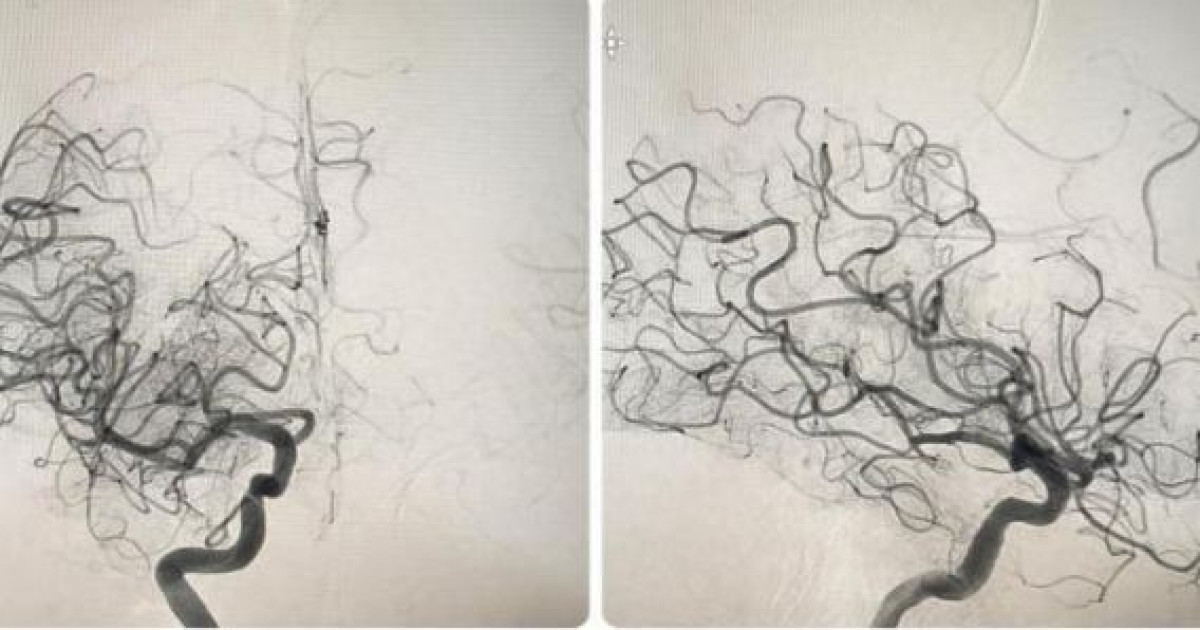

Астанада Ұлттық нейрохирургия орталығында Қытай елінен келген дәрігерлер мен медицина агенттеріне арналған ақпараттық тур өтті.

Адам санасы мың қатпар, жаратылысы жұмбақ. Ғалымдардың әлі күнге пенде баласының мүмкіндіктері мен ми қыртыстарындағы жаңалықтарды зерттеп тауыса алмауы бұл ретте қалыпты дүние десек болады.